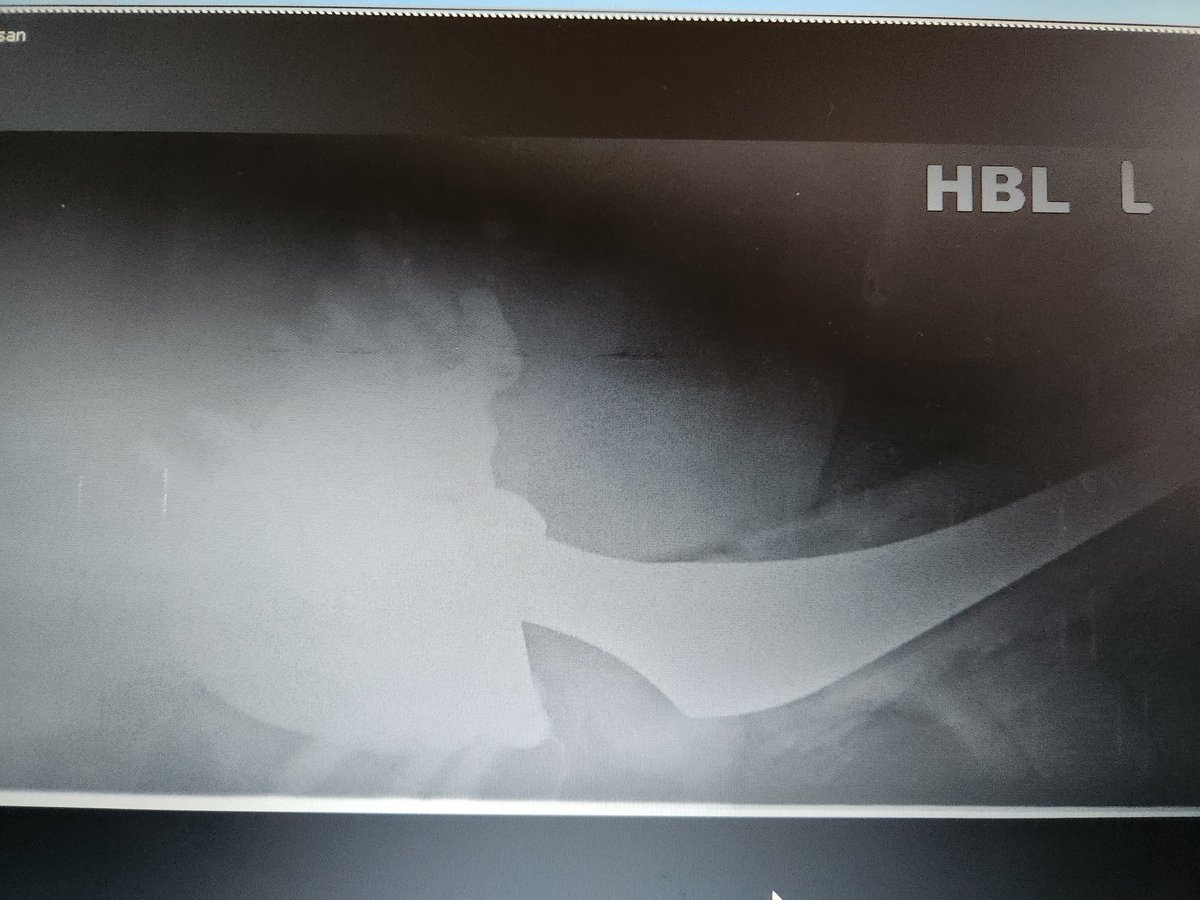

These are expensive too and a lot of hard work goes into getting pt on table. Thank you to YGC theatres & staff for the effort, @BetsiCadwaladr for support, fantastic MDT Wrightington, North Wales MDT, surgical experience @CavendishHip, my colleagues & Mr Kapur for dual operating